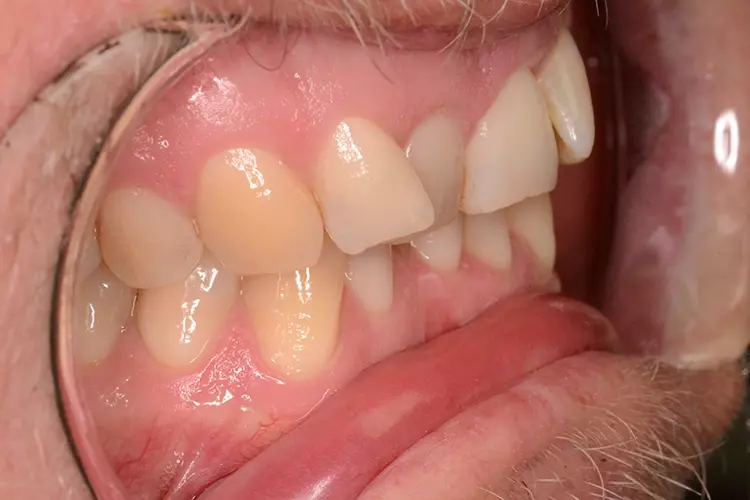

Bei dem heute 49-jährigen Patienten wurde seit Kindertagen versäumt, die Ober- und Unterkieferzahnbögen kieferorthopädisch auszurichten. Der Patient leidet seitdem stark unter seinen Zahnfehlstellungen.

Die Fraktur des stark elongierten Zahnes 21 war für den Patienten der Ausgangspunkt, sowohl die Front des Ober- als auch des Unterkiefers prothetisch überarbeiten zu lassen. Dabei wurde der frakturierte Zahn 21 durch ein navigiert eingesetztes Sofortimplantat ersetzt, während die verschachtelt stehenden Zähne 12 und 42 durch eine Brückenversorgung korrigiert wurden (Abb. 4a-j).